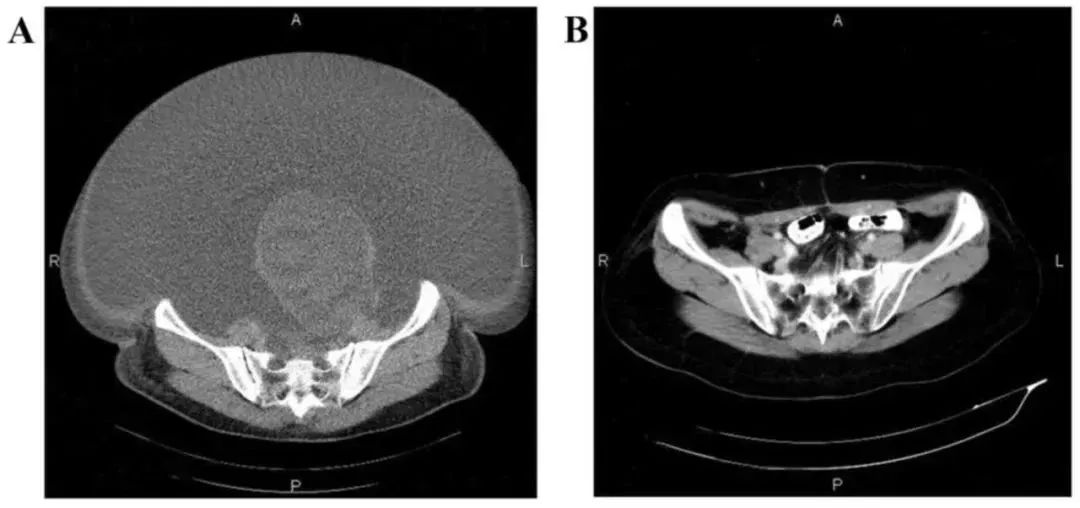

国内一名 60 岁的卵巢癌晚期患者,在接受了体外扩增,高度活化的同种异体 NK 细胞的临床治疗后,CA125 水平从 11,270 降至 580,所有腹水都消失了。此外,CT 扫描的肿块体积减小,并且没有出现副作用。 案例 4: